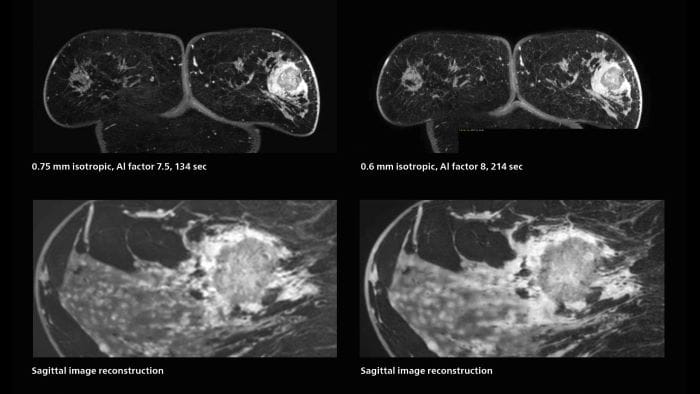

3D MRI of breast cancer

Scanning was performed with two different voxel sizes. AI enabled volume MRI allows image reconstruction in other directions. Biopsy revealed invasive ductal carcinoma in this patient. Performed on Elition X.

Fast AI-enabled MRI of breast cancer: comparing 3D acquisitions with 0.75 mm and 0.6 mm isotropic voxels.

Speed and high image quality are also important factors determining the diagnostic value of breast MRI. “When the spatial resolution is not high enough for making the diagnosis of breast cancer, a very difficult decision must be made,” says Dr. Katahira. “Since SmartSpeed now allows us to increase the resolution, we can often easily provide a confident answer. In the past with SENSE we used 1.2 mm isotropic voxels in breast imaging after contrast admission. With Compressed SENSE that is 0.8 mm. Now with SmartSpeed we can acquire 0.6 mm isotropic voxels and the images are so clear that even tiny details are clearly visible.”

“The use of SmartSpeed has considerably improved our breast cancer imaging, with higher temporal resolution, higher spatial resolution, and higher SNR compared to the past, when we were using just Compressed SENSE. In addition, the dynamic study is now more useful in diagnosis because the ultrafast dynamic scan can be taken every 3 seconds.”